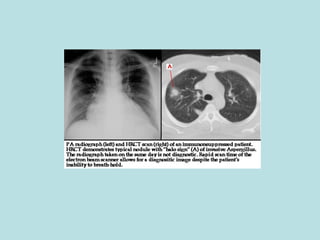

Invasive aspergillosis Most commonly in severely neutropenic e.g. after bone marrow transplant Portal of entry: sinuses, lungs Difficult to diagnose Clinical suspicion, radiology, laboratory tests Difficult to treat Amphotericin B, voriconazole, itraconazole Surgical resection Poor outcome

Invasive aspergillosis Mostcommonly in severely neutropenic e.g. after bone marrow transplant Portal of entry: sinuses, lungs Difficult to diagnose Clinical suspicion, radiology, laboratory tests Difficult to treat Amphotericin B, voriconazole, itraconazole Surgical resection Poor outcome